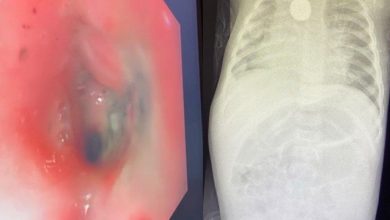

بدون تدخل جراحي استخراج بطارية حارقة من مريء طفلة بولادة مكة

في سابقة علاجية نادرة دون تدخل جراحي، نجح فريق طبي بمستشفى الولادة والأطفال بالعاصمة المقدسة عضو تجمع مكة المكرمة الصحي…